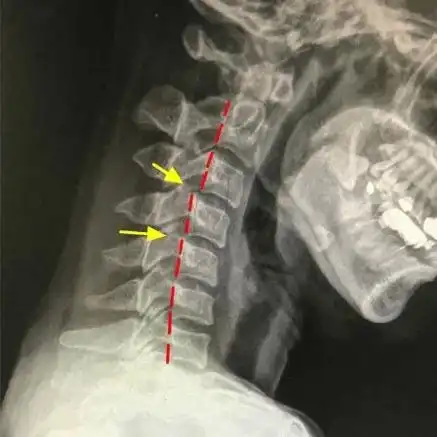

生理曲度变直 学习,补课,网课,同时户外运动减少,孩子脖子经常向前倾

前倾不仅会带来短脖子还改变了身体重心身体为了找平衡只能把骨盆顶